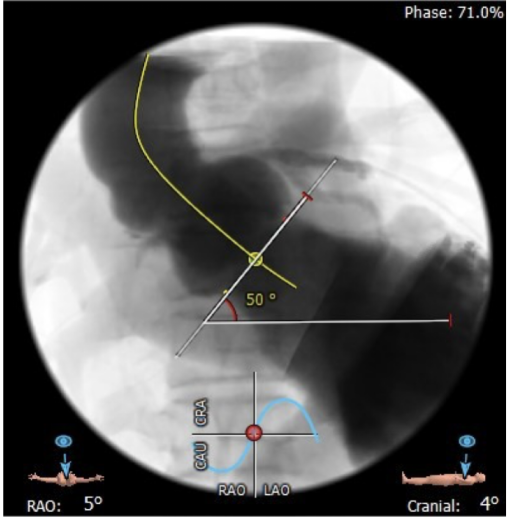

升主动脉直径:31.1mm,心脏夹角:50度